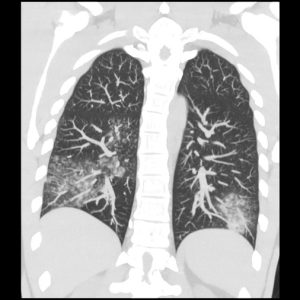

- Pemeriksaan penunjang :

– Rontgen thorax/CT Scan